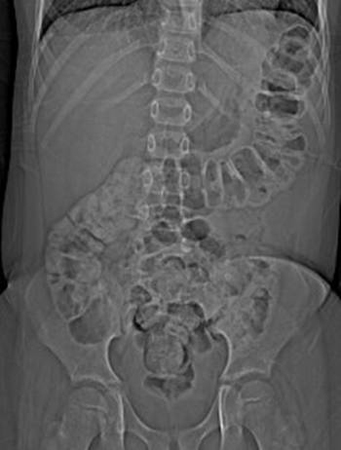

- radiografia abdominal:

fezes visíveis em todo o cólon

Mais - estudo do trânsito colônico do marcador radiopaco:

trânsito colônico lento, como medido pelo atraso no movimento marcador, confirma constipação

- radiografias abdominais simples:

alças dilatadas com nível hidroaéreo secundário ao íleo paralítico; ar livre consistente com a perfuração; no megacólon tóxico, o cólon transverso encontra-se dilatado em 6 cm ou mais de diâmetro

dilatação do intestino delgado ou cólon; calcificação; abscessos intra-abdominais

alças do intestino delgado dilatadas, níveis hidroaéreos em todo o abdome

distensão gasosa do intestino grosso; volvo sugerido por alça intestinal em forma de feijão

alças do intestino dilatadas, pneumatose intestinal, gás na veia porta, ar livre, alça intestinal presa; ausência do padrão de gases normal no intestino